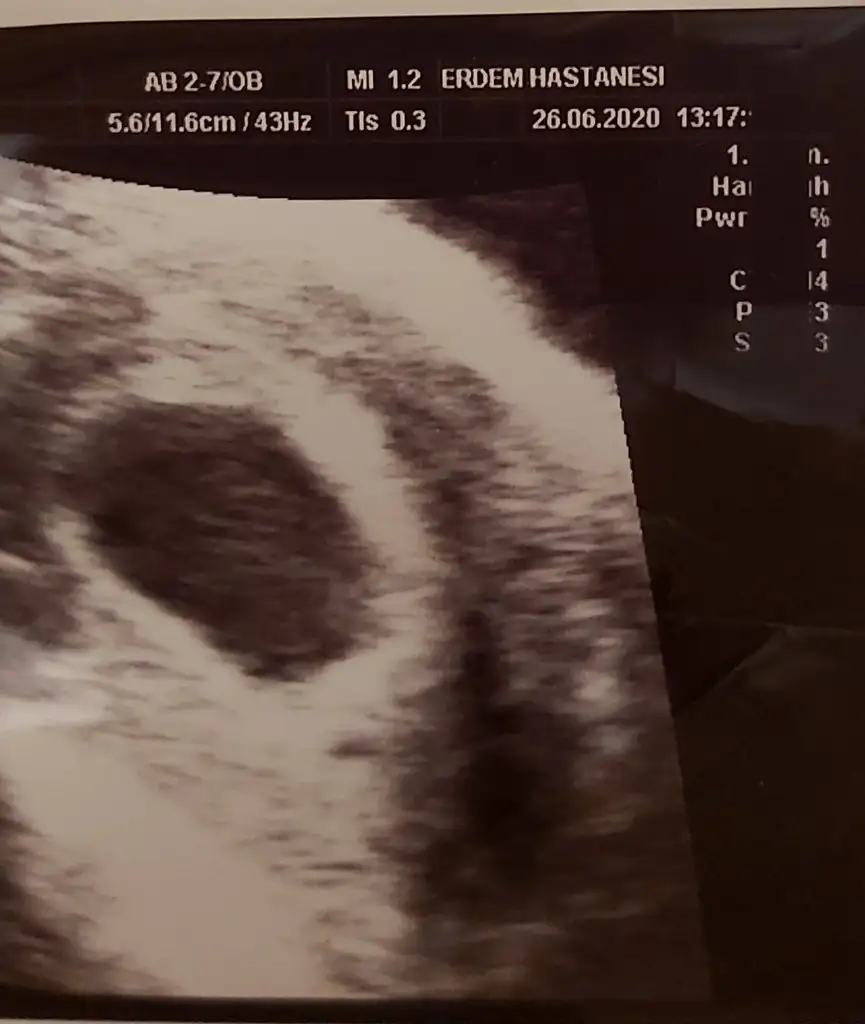

5,5 haftalıkken ultrason görüntüsü. Insallah carşamba günü görürümUltrason görüntüsü varsa atabilir misin?

Acele etme görüceksin Allah ın izniyle.5,5 haftalıkken ultrason görüntüsü. Insallah carşamba günü görürüm![]()

2.hamileliğim. İlki kalbi atmadığı için düşük olmuştu. Şimdi, 5,5 haftalıkken doktor boş gebelik olabileceğinı söyledi. Ama internette 7. Haftata embriyonun oluştuğu ve kalp attığı yazıyor. Doktor 5,5 haftalıkken bunu nasıl anlamış oluyor. Yani kafam çok karışık. Çarşamba bidaha gel bakalım dedi ama o zamanda 6 haftalık hamile oluyorum yine gözükmeyebilir. Moralim çok bozukDaha önce boş gebelik yaşayan oldu mu? Ne zaman anlaşıldı boş gebelik olduğu bunu merak ediyorum.